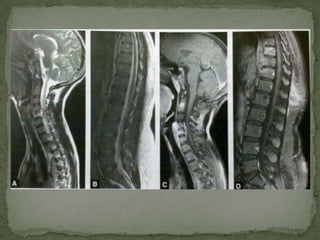

 modality of choice

 advantages –

 multiplanar capability

 the direct demonstration of early bone marrow

involvement or edema

 unsurpassable assessment of spinal canal and neural

involvement

 Soft tissue and Intraosseous abscesses are also well

demonstrated on MR imaging

 Higher sensitivity for early infiltrative disease

including endplate changes and marrow infiltration

than bone scan and plain films

 MRI Scores over CT in-

 Detection of early disease (marrow edema)

 Skip lesions more easily and more often detected.

Incidence of multilevel noncontiguous vertebral

tuberculosis is generally reported to be between 1.1 and 16

%

 Detection of epidural, meningeal and cord involvement

 Planning the surgical approach